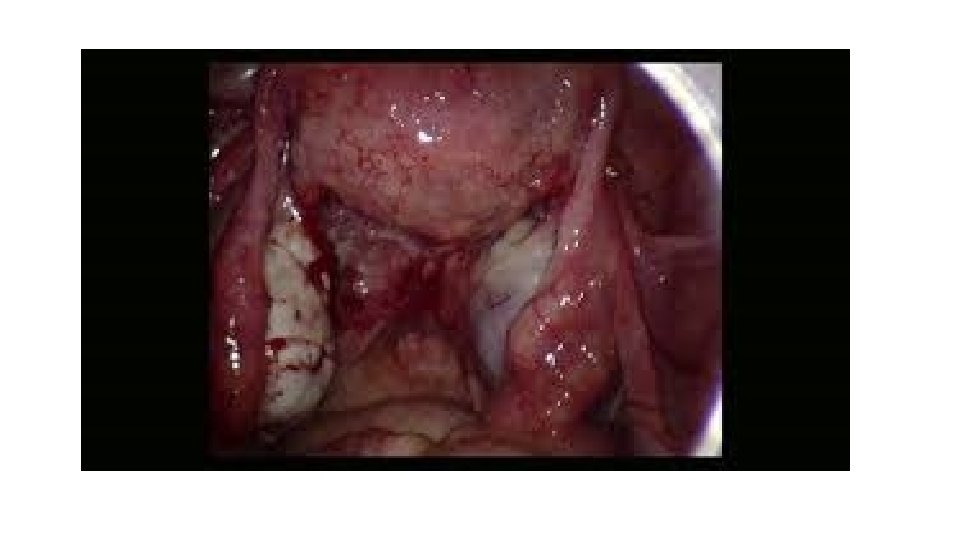

Acute PID Diagnosis: A. History: - recent menstruation - IUD user - invasive gynecological procedure - new sexual relation B. Clinical picture C. Investigations: - blood ( leucocytosis, ESR, CRP) - saline mount of vaginal discharge (excess WBC) - culture of cervical discharge (organism) - D. laparoscopy (erythema, edema, exudate)

Chronic PID Investigations: . Pelvic ultrasound fixed RVF uterus, cystic pelvic mass . HSG tubal obstruction, hydrosalpinx . D laparoscopy pelvic adhesions (frozen pelvis) pelvic mass